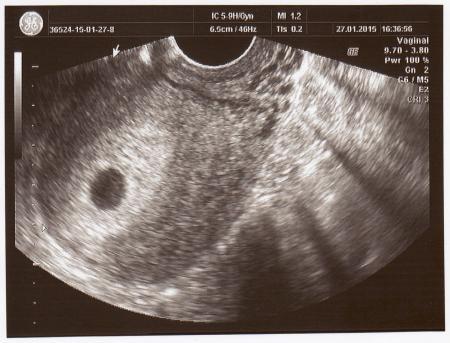

Hallo zusammen, ich weiss gar nicht wo ich als erstes anfangen soll. Ich bin total am Ende, der heutige Tag war für mich ein Horror Trip. So jetzt zur meine Geschichte…. Letzte Woche habe ich durch einen positiven Schwangerschaftstest erfahren, dass ich Schwanger bin. Gestern war ich bei meinem Fa um es bestätigen zu lassen. Es ist meine zweite Ssw und ein weiteres Wunschkind. So schaut bis jetzt alles Super aus, mein Arzt ist sehr zufrieden. Ich habe euch mein Ultraschallbild mit beigelegt. Heute als ich mit meiner kleinen und meiner Mutter zum Shoppen unterwegs war und ich auf Klo war, habe ich gesehen, das ich plötzlich rotes Blut in meiner Unterwäsche habe. Da leider heute Mittwoch ist und mein Fa um 13 Uhr geschlossen hat, sind wir schnell ins Kh gefahren. Eins weiss ich sicher, ich werde nie wieder in dieses Spezielle Krankenhaus gehen =( Als ich meine Daten + Urinprobe angeben habe, kam schon die unsensible Frau von Ärztin rein und hat mich so grob untersucht, das ich glatt unten gerissen bin. Das war aber nicht das schlimmste, sie meinte dass ich mich nicht so anstellen soll wenn ich es verliere, da ich schon ein Kind habe. Dann meinte sie, dass es nicht gut ausschaut, da sie noch nichts sehen kann, wohlgemerkt bei meiner ersten Schwangerschaft haben wir in der 6Ssw auch noch nichts gesehen sondern erst drei Wochen später. Dann hat sie mich glatt noch an gemault, wieso ich noch keinen Mutterpass habe sondern nur ein Ultraschallbild. Mein Fa gibt ihn mir erst drei Wochen später, wenn wir mehr wissen. Diese Odyssee ging dann noch weiter… Ich bin so mit den Nerven am Ende, ich habe so große Angst mein Würmchen zu verlieren. Sie konnte mir nicht mal so richtig beantworten, woher ich die Blutungen habe und was es für Auswirkungen haben könnte. Sie meinte nur entweder verlieren sie es oder nicht. Ich wäre nicht die erste Frau. Die Blutungen haben seit 4 St. aufgehört, ein leichtes ziehen habe ich noch aber das hatte ich schon ab und zu mal. Was meint ihr zu dem ganzen? Danke für eure Zeit!!!

Huhu zusammen =) Erstmal vielen Dank für eure zahlreichen Antworten. Ich war vorhin bei meinen Fa und es ist alles OK =) heute haben wir sogar das kleine Herzchen pulsieren gesehen =) (Bild ist im Anhang) Ich werde auf jeden Fall eine beschwerde an das Kh schreiben. Es wundert mich das die Frauenärztin gestern angeblich nichts gesehen hat, wenn mein Fa es heute schwarz auf weiss hat. Die Blutungen kommen auf jeden Fall von weiter oben, ich soll mich die Woche einfach auskurieren und wenig wie möglich machen. Lg Jadya